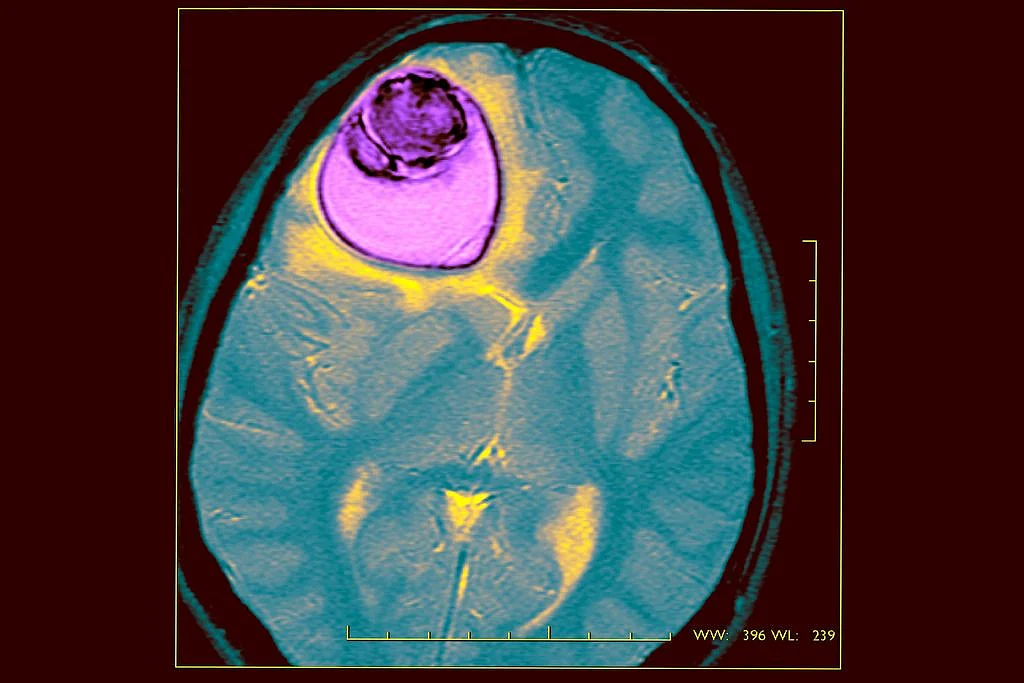

An Indian girl who was mysteriously paralysed down one side of her body was operated on by doctors where they found a tape worm cyst almost half the size of her brain.

Finally, her parents had to sell their gold jewellery to take her to a specialist neurosurgeon Dr Solanki in Gujarat where it was discovered that she had a hydatic cyst from an intestinal tapeworm.

He said to the Daily Mirror, "I believe the hydatid cyst had been slowly growing in the girl for the past eight to 10 years. But as it got bigger it had more affect on her day to day life and her headaches were getting worse."